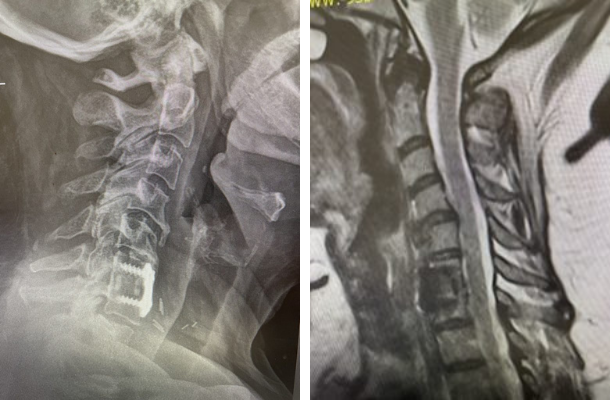

Figure 1: Sagittal x-ray after C6-7 anterior cervical discectomy showing collapse of the C5-6 disc space with fully connected anterior bridging osteophyte and C4-5 partially bridged anterior osteophyte with anterior angulation of C4 vertebral body. Sagittal T2-weighted MRI showing listhesis of C4 on C5 with C4-5 disc protrusion causing cord compression.

On the initial visit she was completely neurologically intact. We recommended physical therapy and ordered cervical x-rays and MRI (Fig 1). It appeared on her x-rays that she had a stable C6-7 fusion segment, but she also had a very collapsed C5-6-disc space. In front of that C5-6 disc space there is an obvious anterior osteophyte bridging the space, in essence autofusing that segment. Right above that at the C4-5 space there was an anterior bridging osteophyte as well with some C4 anterior angulation and listhesis with respect to C5, although the bridging bone did not completely bridge across to C5. Since C6-C7 and C5-6 were essentially non functional, there was biomechanical stress on the next segment, C4-5, which resulted in premature degeneration and instability. This also on MRI caused more stress on the C4-5 disc segment and secondary protrusion with anterior cord distortion. Given this was only a static picture of her spine, imagine how her cord is affected on flexion and extension movements.